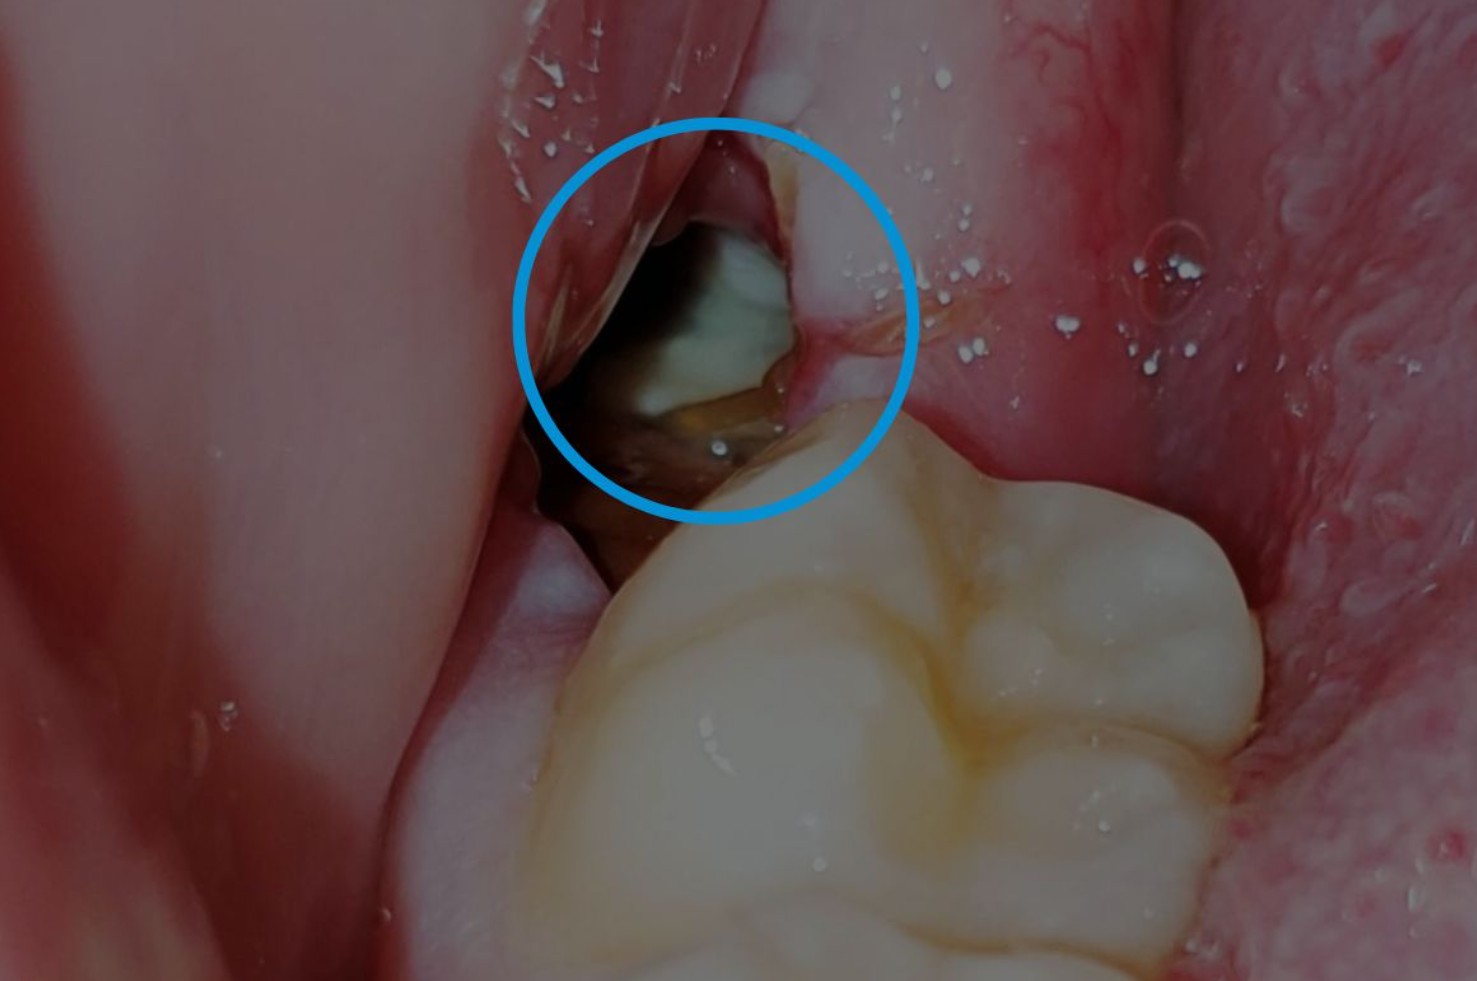

3. Trường hợp mọc răng khôn ngầm, mọc lệch, mọc kẹt

Đây là tình huống khá phổ biến, đặc biệt ở người có hàm nhỏ hoặc răng khôn mọc muộn.

Một số dạng mọc sai vị trí thường gặp gồm:

- Răng mọc ngang: thân răng nằm song song với xương hàm, đâm vào răng số 7.

- Răng mọc xiên hoặc nghiêng ra má: gây đau, trầy niêm mạc, viêm lợi.

- Răng mọc kẹt trong xương: chỉ trồi lên một phần, tạo khe hở dễ tích tụ thức ăn.

Hậu quả nếu không phát hiện và xử lý sớm có thể gồm:

- Đau nhức, sưng nướu, khó há miệng.

- Viêm quanh thân răng khôn, áp xe vùng hàm.

- Sâu răng số 7 do răng khôn mọc sát gây đọng thức ăn.

- Gây chen chúc, xô lệch khớp cắn hoặc làm nghiêng răng kế cận.